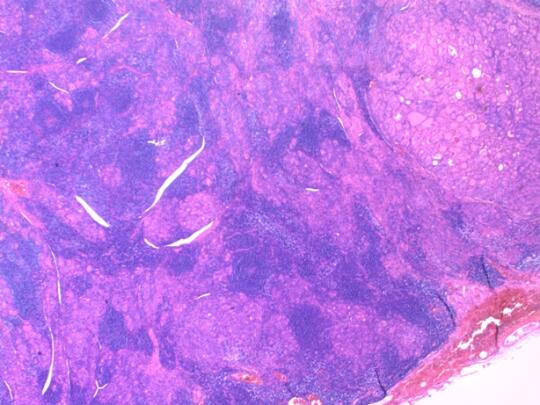

图3和图4:显微镜观察

图3低倍镜下:整个腺体结构几乎被淋巴细胞浸润所取代,右上角仍残留一小块正常腺泡组织。

图4高倍镜下:大片一致性的小型淋巴细胞包围着零星残余的甲状腺滤泡(右下角),正常甲状腺的组织结构被严重破坏并替代。